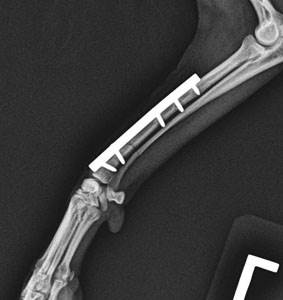

Большинство переломов у домашних животных требуют хирургической стабилизации – операция, которая служит для соединения отломков кости, называется остеосинтез.

Закрепление костных отломков осуществляется при помощи различных фиксаторов – внутрикостных штифтов, пластин, закрепляемых винтами, аппаратов внешней фиксации (спицы или аппарат Илизарова), проволочного серкляжа или сочетания этих методов.

Главная задача операции – обеспечить стабильную фиксацию костных отломков друг относительно друга в анатомически верном положении, и неподвижность зоны перелома до наступления полного сращения.

Хирургический метод лечения (остеосинтез)

у животных является наиболее эффективным и применяется наиболее часто, так как у собак и кошек практически отсутствует возможность использования таких методов консервативного (безоперационного) лечения, как скелетное вытяжение и крайне ограничено применение гипсовых повязок и других иммобилизационных приспособлений.

В зависимости от расположения и типа фиксатора различают внутренний (погружной) остеосинтез (накостный, внутрикостный, чрескостный) и наружный чрескожный (метод Илизарова) и его модификации. Выбор метода хирургического лечения перелома определяет ветеринарный врач исходя из особенностей травмы, сложности перелома, индивидуальных особенностей животного (размер, возраст, состояние костной ткани, темперамент).